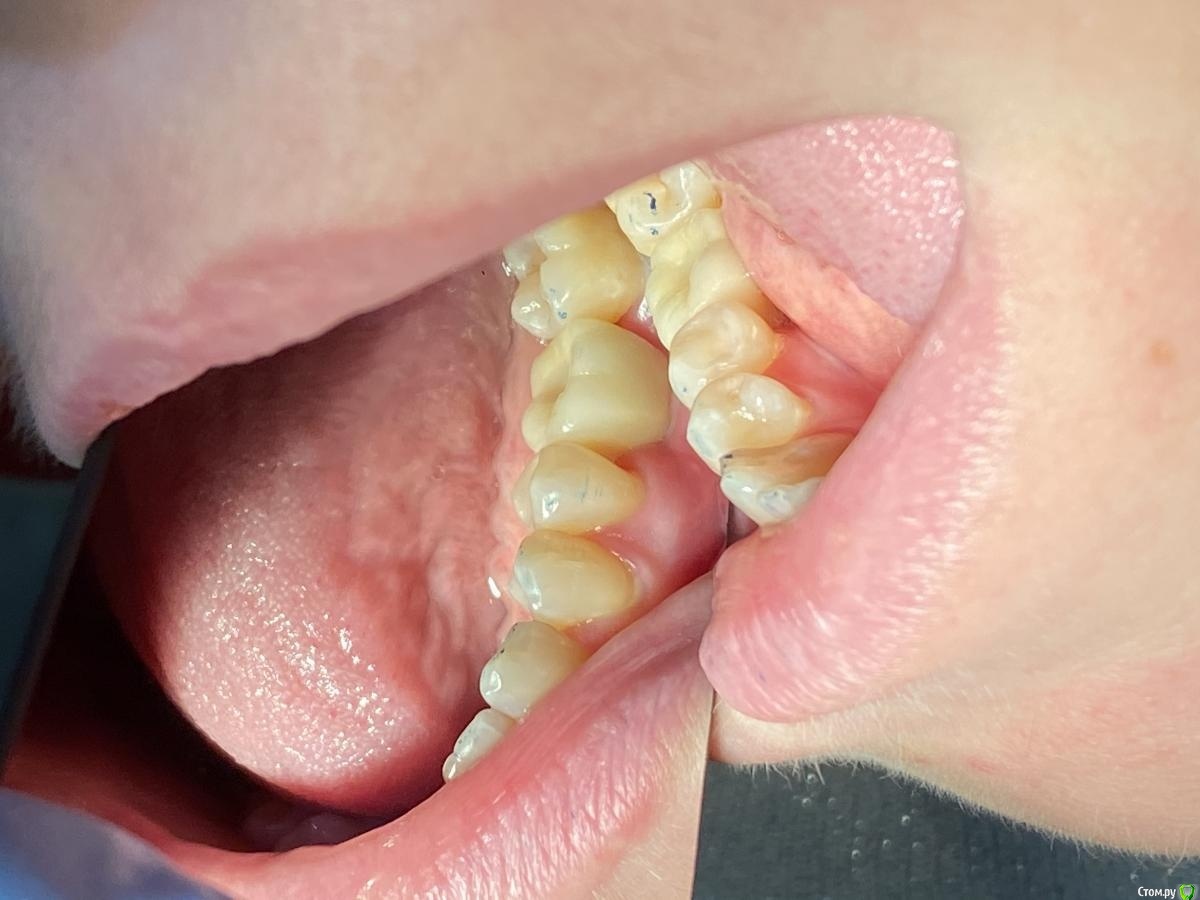

Женька Опубликовано 14 сентября, 2020 Автор Поделиться Опубликовано 14 сентября, 2020 Ну как-то вот так... Ссылка на комментарий

Irouil Опубликовано 14 сентября, 2020 Поделиться Опубликовано 14 сентября, 2020 (изменено) Не идеально, конечно, но я бы отправил уже на протезирование так на Вашем месте, прикрепленка есть, кортикалка по шейку Если включать перфекциониста, то можно пончо сделать, но нужно отслоиться через прикрепление эпителиальное, нужно и увеличение, и тунельный острый инструмент или микро хирургическое лезвие, и навык. Испортить тут можно гораздо больше, чем улучшить Основание абатмента пониже и пошире просто взять и пациента натаскать на гигиену, все ок будет Изменено 14 сентября, 2020 пользователем Irouil 1 Ссылка на комментарий

Женька Опубликовано 14 сентября, 2020 Автор Поделиться Опубликовано 14 сентября, 2020 Не идеально, конечно, но я бы отправил уже на протезирование так на Вашем месте, прикрепленка есть, кортикалка по шейку Если включать перфекциониста, то можно пончо сделать, но нужно отслоиться через прикрепление эпителиальное, нужно и увеличение, и тунельный острый инструмент или микро хирургическое лезвие, и навык. Испортить тут можно гораздо больше, чем улучшить Основание абатмента пониже и пошире просто взять и пациента натаскать на гигиену, все ок будетЯ придерживаюсь этого же мнения...Я скорее испорчу то, что получилось. Эти фото с формирователем 4.5, 3 месяца ходили с 4.0На этапе прикручивания 4.5, пациентка отметила легкое жжение... на фдм метрогил был...вот думаю, то ли это на метрогил такая реакция, то ли я что-то задавил? Планировали на тибейзе geo делать... там варианта пошире насколько я знаю нет. 4.5 и размеры по вертикали cut и длинные З.Ы. Вчера у Ильгама Ирековича на курсе впервые познакомился с галилеями от экзама... всего 2.8, быстро привыкли глаза (учитывая, что они не индивидуально под меня были)... это просто какой-то другой мир. Ссылка на комментарий

Марья Моревна Опубликовано 14 сентября, 2020 Поделиться Опубликовано 14 сентября, 2020 Там на пятерке у пломбы с краевым прилеганием и экватором вопросы, лучше решить это до протезирования. Ссылка на комментарий

Женька Опубликовано 15 сентября, 2020 Автор Поделиться Опубликовано 15 сентября, 2020 Там на пятерке у пломбы с краевым прилеганием и экватором вопросы, лучше решить это до протезирования.Там кариес вторичный завелся уже и пятно на семёрке.Хотели во время интеграции залечить... но не сложилось) конечно решим до протезирования Ссылка на комментарий